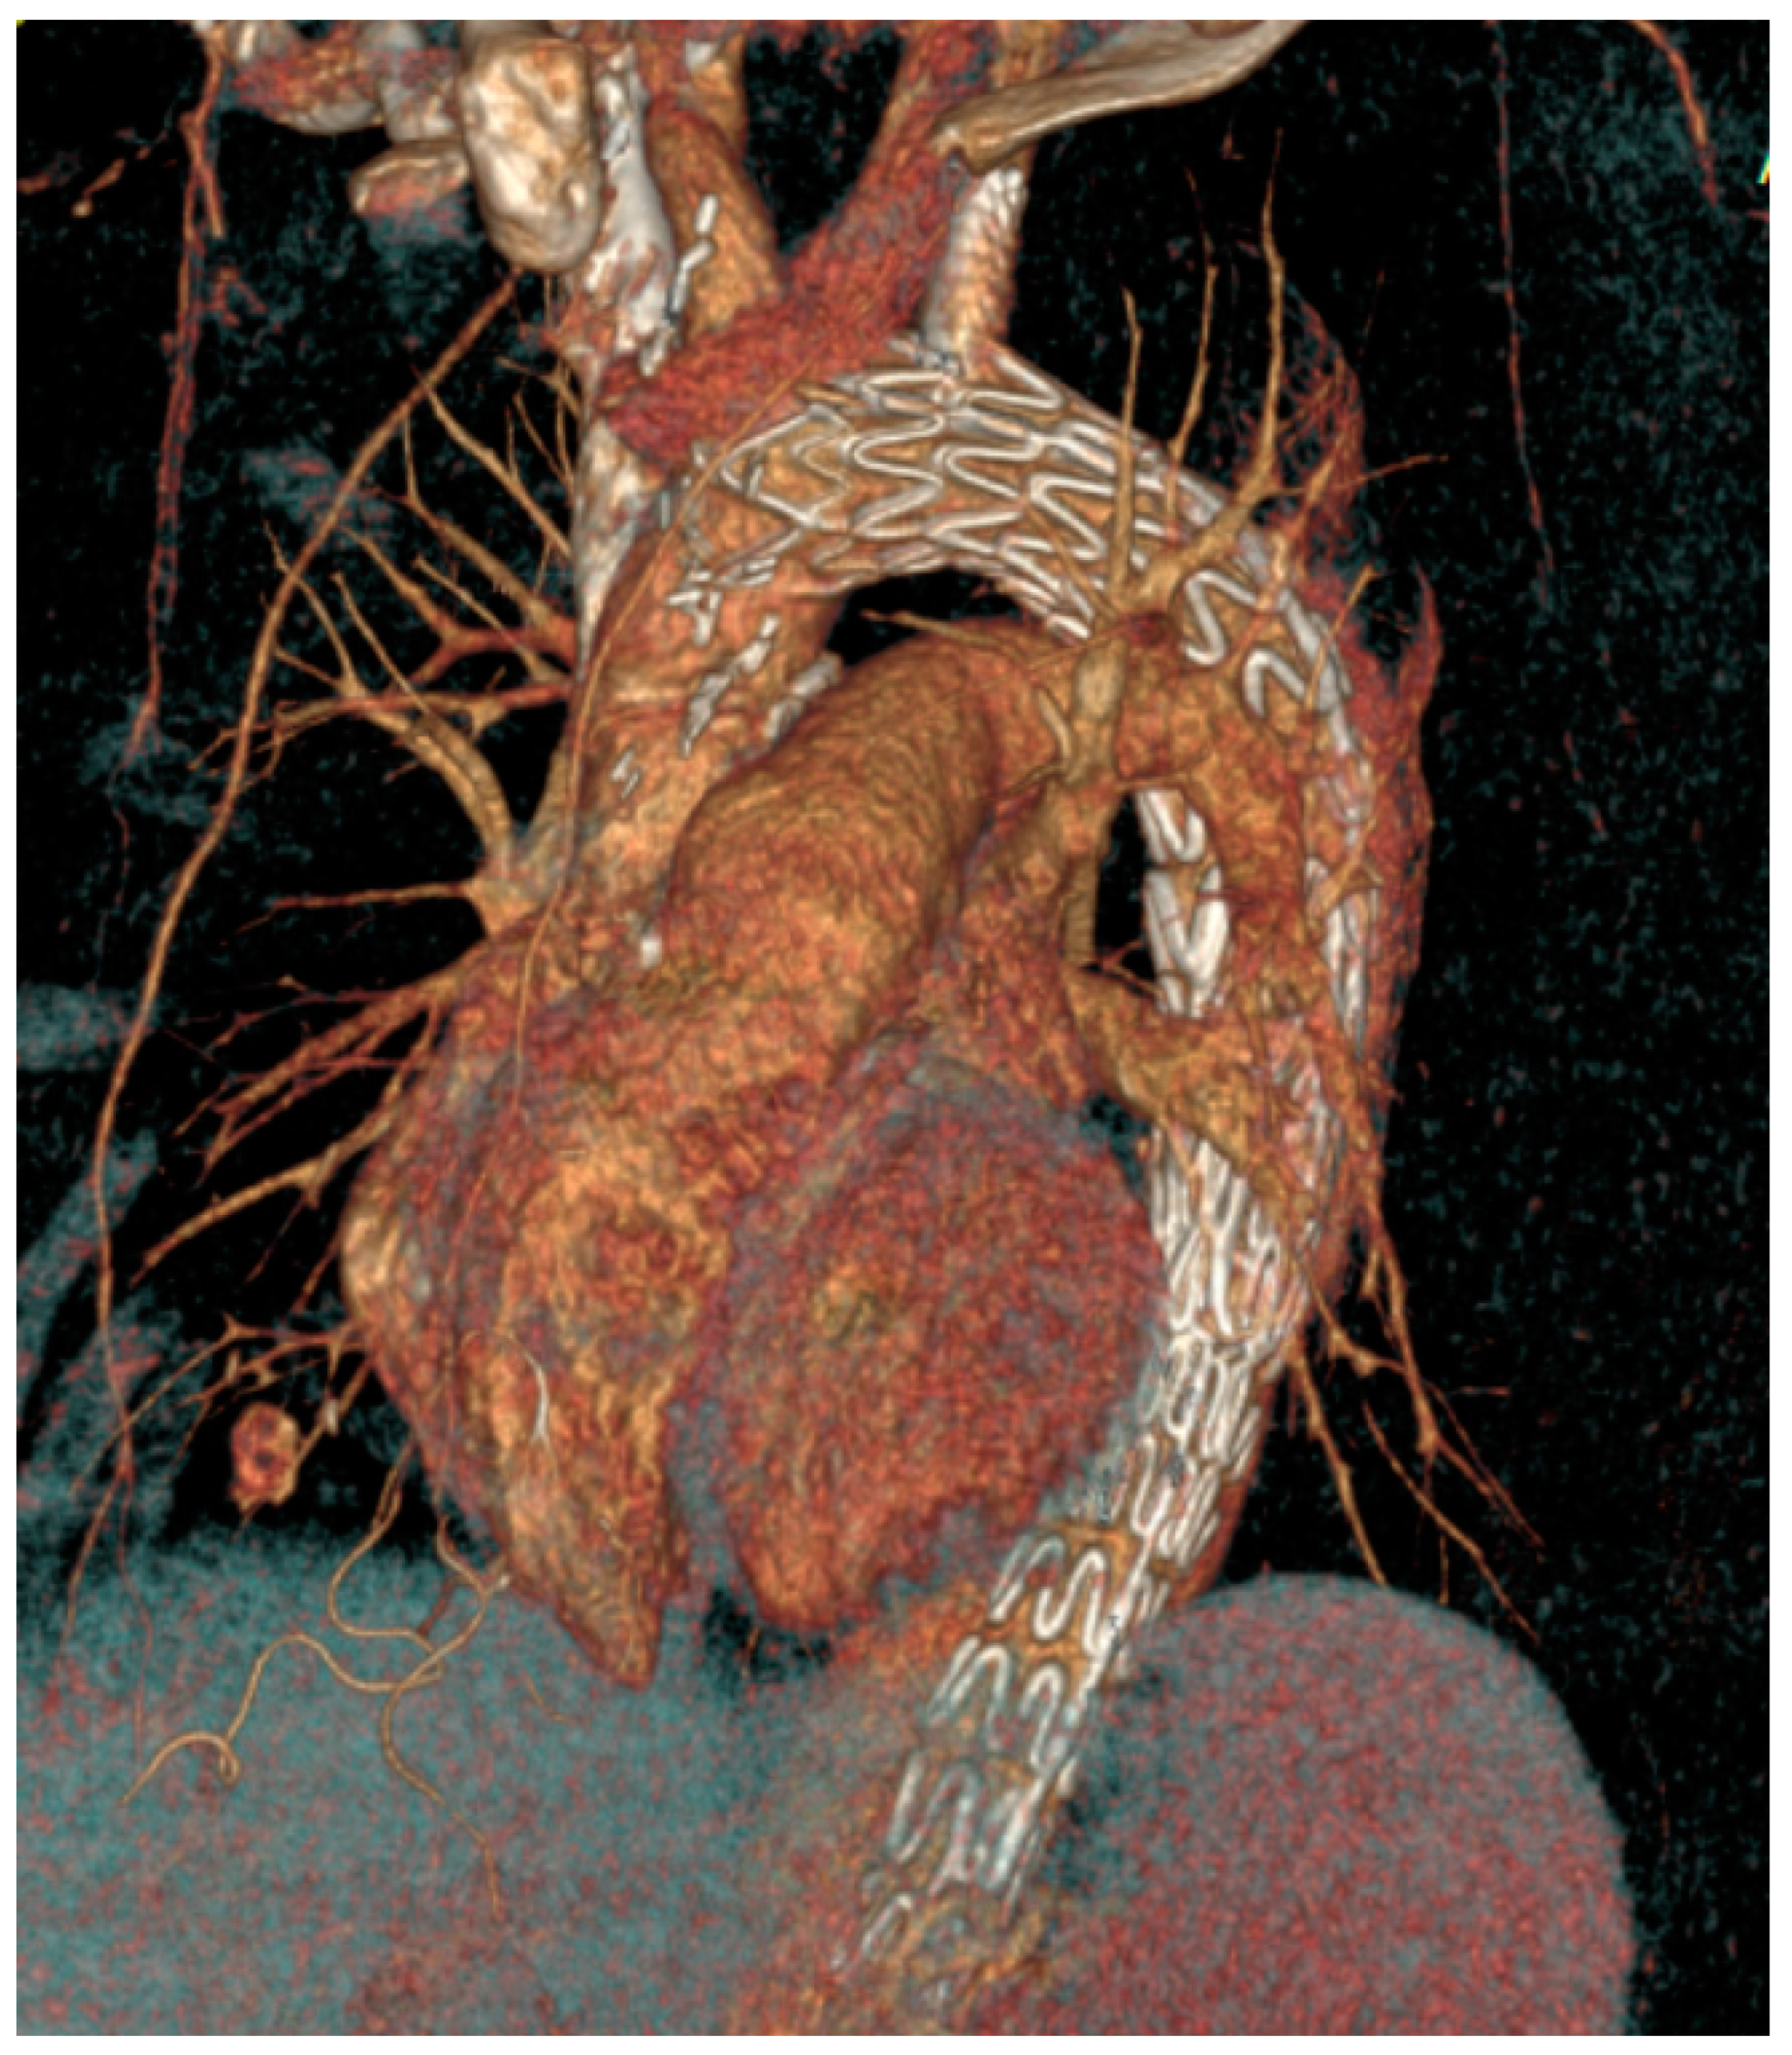

General anesthesia was administered. Vascular access was achieved through the common femoral artery via a cut-down. The FuThrough puncture system (Lifetech Scientific, Shenzhen, China) is designed with a self-centering balloon catheter and an adjustable 20-gauge needle. The puncture system for left subclavian artery (LSA) fenestrations was introduced via the left brachial artery, with an additional cut-down at this site. In situ needle fenestration (ISNF) was initiated following the deployment of the endograft. A steerable sheath (Fustar-Lifetech Scientific, Shenzhen, China) is inserted through the brachial access. The sheath is carefully positioned to be as perpendicular as possible to the greater curvature of the aortic arch, ideally making direct contact with the outer curvature of the thoracic endograft. To ensure stability, the balloon at the tip of the adjustable puncture needle is inflated, with the penetration depth pre-set on the device. The fenestration process involved passing a 0.018 or 0.035 guidewire through the puncture site (advanced into the ascending or descending aorta), which was then widened with a small-sized balloon (4–6 mm). Subsequently, the ISNF is connected with a balloon-expandable chrome cobalt ePTFE stent graft (BeGraft-Bentley, Hechingen, Germany), oversized by about 10%, and potentially antegrade up to 5 mm within the fenestration. The angiographic images during the procedure are shown in Figure 3, and Figure 4 shows the postoperative CT angiography 3D image. The Ankura stent graft was selected for all ISNF group cases due to its properties that facilitate easy puncture and dilatation. This choice was based on its ability to accommodate the technical requirements of ISNF effectively. (Figure 3 and Figure 4).

Figure 4. Postoperative computed tomography angiography (CTA) 3D image after the in situ needle fenestration thoracic endovascular aortic repair (TEVAR) procedure.